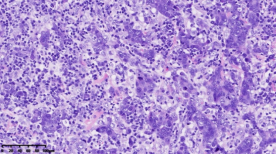

在本項(xiàng)研究中,研究人員利用基本的組織形態(tài)學(xué)方法及免疫組織化學(xué)法對(duì)TNBC進(jìn)行分型:腔面雄激素受體型(LAR)(圖1A),免疫調(diào)節(jié)型(IM)(圖1B),基底樣免疫抑制型(BLIS)(圖1C),間充質(zhì)型(MES)(圖1D)。評(píng)價(jià)各亞型臨床病理參數(shù)(如發(fā)病年齡、腫物大小、淋巴結(jié)轉(zhuǎn)移等),組織形態(tài)學(xué)(腫物中央:坌緯、浸潤(rùn)模式、腫瘤間質(zhì)浸潤(rùn)淋巴細(xì)胞、細(xì)胞排列方式、細(xì)胞核形態(tài)、核分裂計(jì)數(shù)、間葉化生等)以及免疫表型(p53、Rb、PD-L1、MMR等),結(jié)果顯示:1.TNBC分型的臨床病理、組織形態(tài)學(xué)和免疫表型特征不盡相同,有望成為復(fù)雜的基因表達(dá)譜分析的替代選擇,為TNBC的分型治療及靶向治療提供理論依據(jù);2.生物標(biāo)記物 PD-L1作為重要的生物學(xué)指標(biāo),對(duì)個(gè)體化治療及免疫治療有重要的臨床指導(dǎo)價(jià)值;3.乳腺癌中dMMR作為一個(gè)低頻發(fā)生事件,不太可能作為免疫治療有效性的評(píng)估手段。該成果發(fā)表在Virchows Archiv期刊,題目為“Subclassifying Triple-Negative Breast Cancers and Its Potential Clinical Utility”。文章DOI為:10.1007/s00428-022-03329-0。

圖1. 基于組織形態(tài)學(xué)及免疫組織化學(xué)標(biāo)記物的TNBC分型